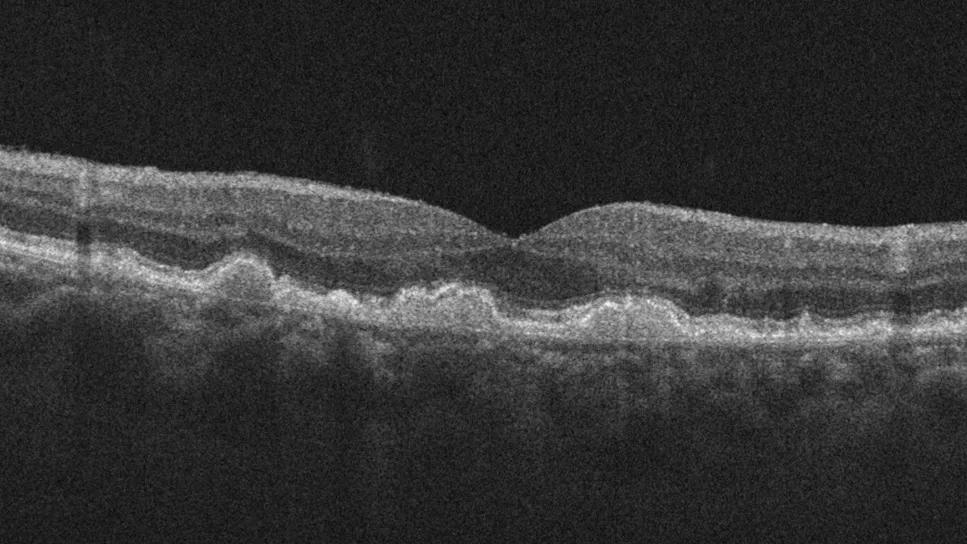

Optical coherence tomography image showing macular fluid

Real-World Results: High-Dose Aflibercept Reduces Macular Fluid, Maintains Vision in nAMD

New insights on effectiveness in patients previously treated with other anti-VEGF drugs